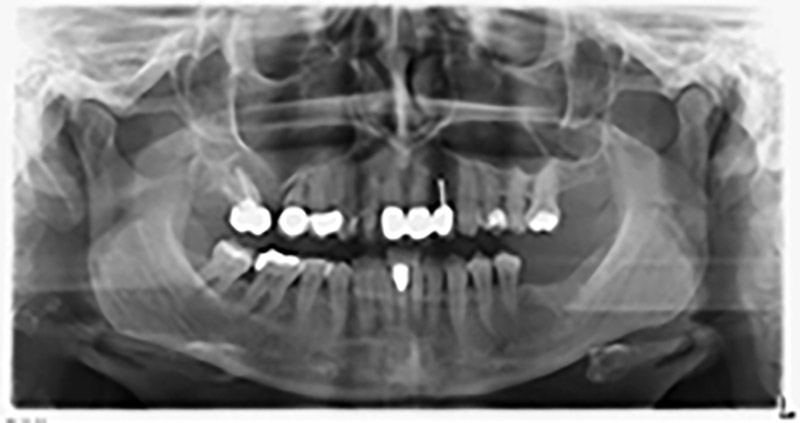

Orthopantomogramm

Abb. 20: Orthopantomogramm nach Behandlung